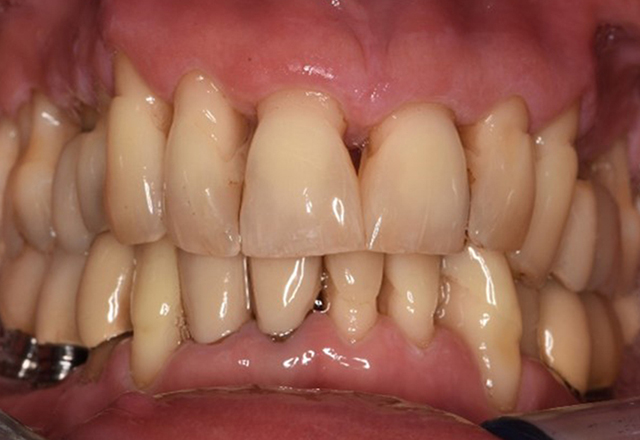

Paciente sana con enfermedad periodontal previa

La paciente de 68 años no tiene enfermedades previas relevantes de la salud general ni toma medicación; sus hábitos alimentarios tampoco suponen un riesgo especial. La paciente tiene dos implantes (tercer cuadrante, desde hace cinco años) y una enfermedad previa periodontal (periodontitis en etapa IV, grado B) con pérdida dental. Actualmente las condiciones periodontales son estables, pero la periodontitis aumenta de manera determinante las complicaciones biológicas cuando se realizan implantes y puede ocasionar la pérdida de un implante (21). Para la sesión de profilaxis se hacen cuatro recomendaciones. más información